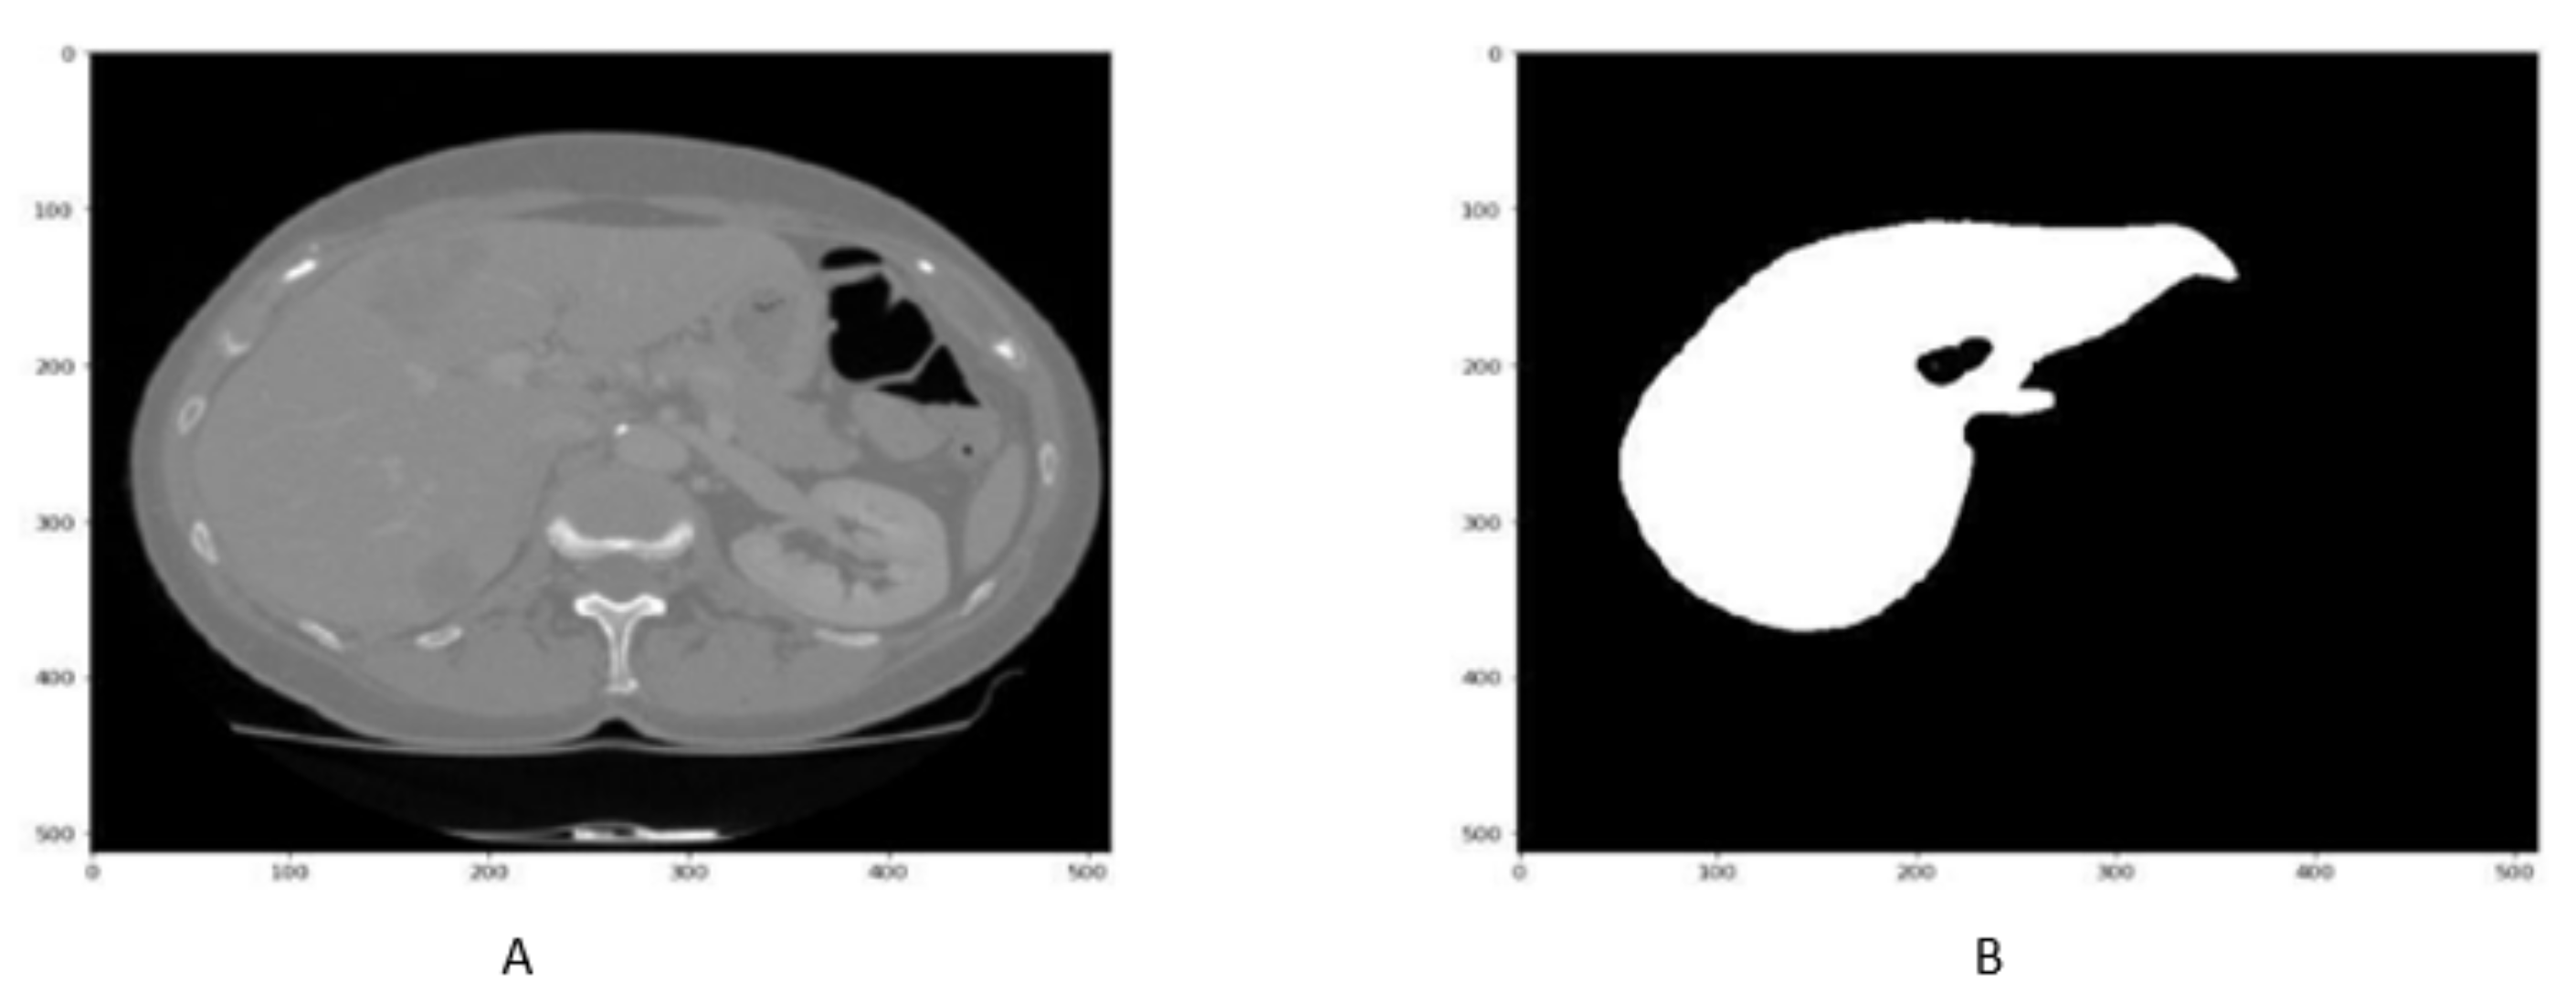

In order to enhance the visualization of the liver, HU windowing is performed at each slice where the HU range of −100 to 400 is selected, as shown in Figure 2. It shows that most organs are occluded in CT image slices without windowing operation, while the image and organs became clearer after HU windowing. Therefore, this HU windowing is performed over all slices before passing them to the next process.

Figure 2.

Figure represents the HU windoing results in (A,B), While Figures (C,D) shows the HU windowing results not having Liver.

Although HU windowing provides good visualization of organs, it was still difficult to differentiate between the liver and adjacent tissues. Therefore, histogram equalization was applied to the image obtained after window processing and then normalized in the range of [0, 1] as shown in Figure 3. It can be seen that as compared with Figure 2A,B, the organs boundaries are more evident in Figure 3C,D after histogram equalization.

Figure 3.

Figure shows that the CT slice (A,B) before histogram equalization, While CT slice (C,D) after histogram equalization.